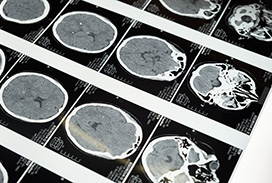

2023 London Imaging Discovery Day